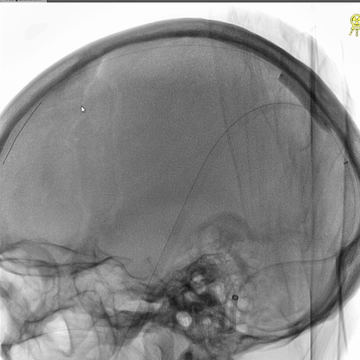

经微导管送入并释放取栓支架(S AB 6*30mm),并在直窦取栓一次,取出少量碎小红色血栓。

微导管配合下,微导丝通过长段慢性血栓进入上矢状窦前部真腔,后交换出微导管。

3*30mm球囊扩张上矢状窦中前部管腔,辅以球囊滑动技术。

4*30mm球囊扩张上矢状窦中前部管腔,辅以球囊滑动技术。

5*30mm球囊扩张上矢状窦和右侧横窦-乙状窦,辅以球囊滑动技术。

中间管造影:上矢状窦中后部和右侧横窦-乙状窦血液引流可。

微导丝微导管再次超选直窦,造影示直窦近段狭窄。

3*30mm球囊再次扩张直窦近段,辅以球囊滑动技术。

球囊扩张直窦后造影:直窦近段仍见狭窄。

微导管造影示:右侧横窦-乙状窦仍见明显狭窄。